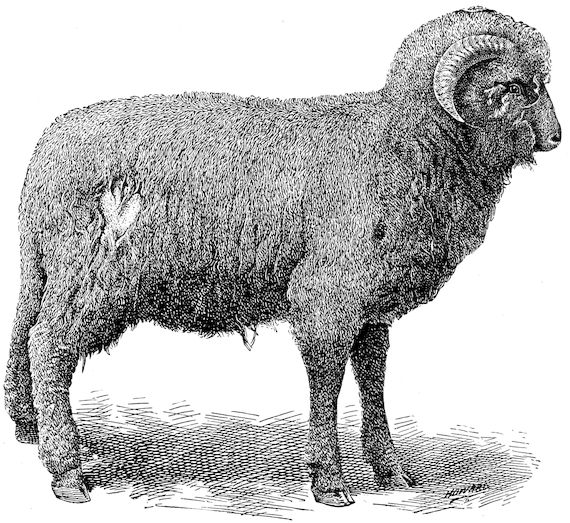

Fig. 2.—Horse suffering from osseous cachexia.

Fig. 3.—Pig suffering from osseous cachexia (fourth stage).

In horses, particularly in riding horses, fractures are commonest in the region of the forearm, cannon bone, and anterior phalanges. So extremely fragile are the bones at this stage that the horse represented herewith broke twelve ribs at one time by simply falling on its side. It is interesting to note that such fractures are never accompanied by any extensive bleeding. They have little tendency to repair, no real callus formation occurs, and on post-mortem examination one often finds the ends unconnected by temporary callus, worn, and rounded by reciprocal friction.

Fig. 4.—Deformity of the face in the horse shown in Fig. 2.

Fig. 6.—Osseous cachexia. This condition developed in two months, the last month of gestation and the first of lactation.